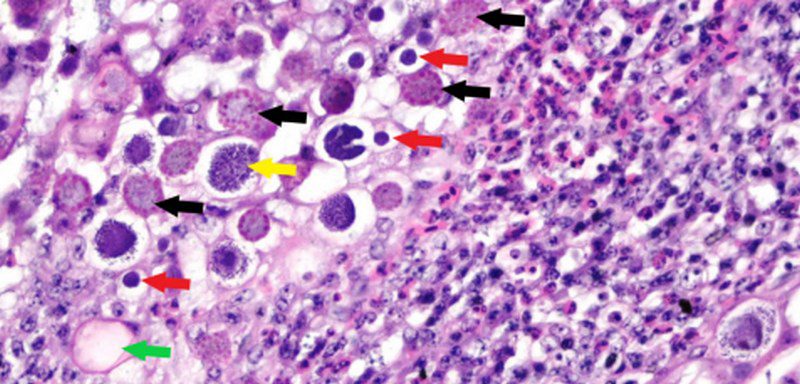

در سطح بافتی، برای تشخیص مراحل تکاملی Eimeria از نمونهبرداری روده (بهویژه دئودنوم، ژژونوم، ایلئوم و سکوم) و رنگآمیزی با هماتوکسیلین–ائوزین (Hematoxylin–Eosin) و PAS

(Periodic-Acid Schiff)استفاده میشود تا شیزونتها، گامتها و مراحل جنینی دیگر دیده شوند.

در مطالعات آسیبشناسی، مراحل تکاملی Eimeria مثل شیزونتها یا گامتها در اپیتلیوم مخاط روده مشاهده شدهاند که منجر به تخریب بافت مخاطی، تغییر ساختار پرزهای رودهای و کاهش توان جذب مواد مغذی میشود.

پس از ورود اوسیستهای اسپوره شده به دستگاه گوارش، Eimeria مراحل پیچیدهای از چرخه زندگی خود را طی میکند که شامل شیزوگونی (تقسیم غیرجنسی) و گامتوگونی (تولید گامت) است. این مراحل داخل سلول مخاطی روده رخ میدهند و باعث تخریب اپیتلیوم و زیرمخاط میشوند.

در نوع سکومی کوکسیدیوز، آسیب به مخاط روده کور (سکوم) بسیار شدید است، به طوری که مراحل تکاملی Eimeria tsunodai با تعداد بسیار بالا درون اپیتلیوم سکوم دیده شدهاند.